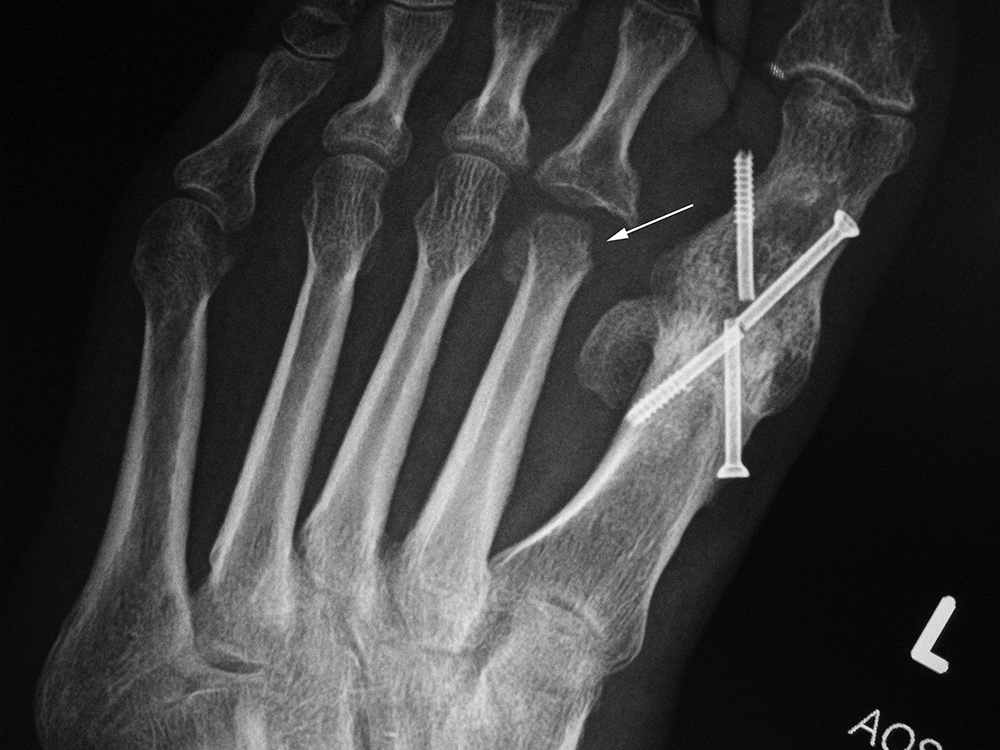

Left first metatarsophalangeal joint arthrodesis screw fractures |

52 year-old man with chronic wound on plantar surface of the left foot and poliomyelitis of the left 2nd metatarsal head (arrow). There is incidental fracturing of two fixation screws from past large toe MTP joint arthrodesis. |